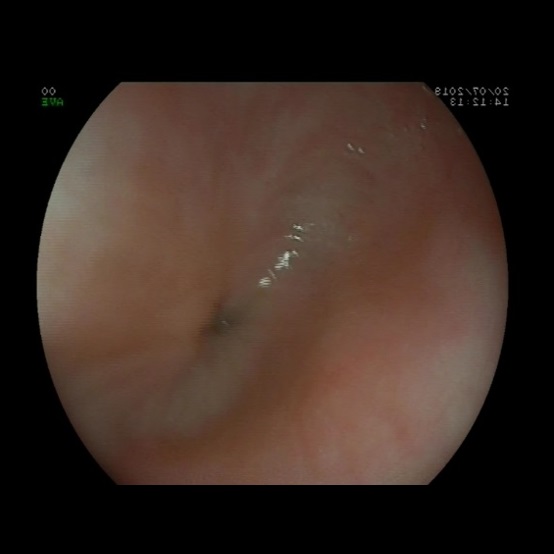

Como parte del estudio se realiza un estudio analítico y una ecografía abdominal, que no muestran alteraciones. Dada la persistencia del cuadro de vómitos, se decide realizar una endoscopia digestiva alta (Fig. 1) en la que se evidencia una estenosis esofágica que impide el paso del endoscopio. El tercio proximal del esófago se muestra dilatado, sin estrías ni anillos. Se completa estudio con tránsito digestivo superior (Fig. 2), donde se confirma estenosis esofágica en el tercio medio-distal, con escaso paso del contraste. En la anatomía patológica de la mucosa se observan cambios inflamatorios de características inespecíficas, sin metaplasia intestinal.

La endoscopia suele mostrar un estrechamiento concéntrico, sin alteraciones macroscópicas en la mucosa4. La histología de la mucosa también debe ser normal, sin datos de reflujo, esofagitis péptica o esofagitis eosinofílica. Por este motivo, esta entidad debe ser sospechada siempre que exista una estenosis con visualización de una mucosa normal4.